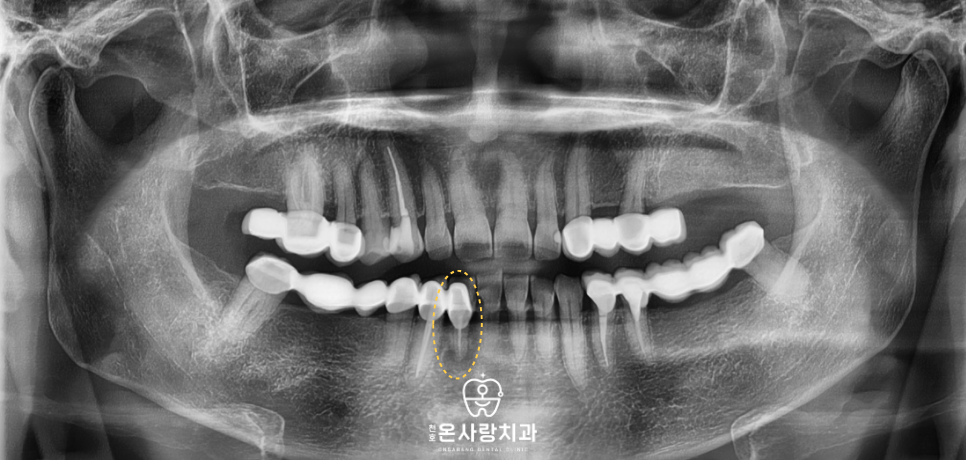

저희는 환자분의 장기적인

저작 기능을 회복하기 위해

기존 브릿지를 절단하고

각 치아의 상태를

재평가하기로 결정하였습니다.

먼저 상태가 매우 좋지 않았던

하악의 앞니 치아는 브릿지를

절단한 이후 발치를 진행하였습니다.

반면 송곳니 치아는 뿌리와

전반적인 치질 상태가

양호한 것으로 판단되었습니다.

따라서 해당 치아는 무리하게

발치하지 않고 크라운 보철물을

새롭게 제작하여 씌워줌으로써

본래의 기능을 유지하도록 하였습니다.